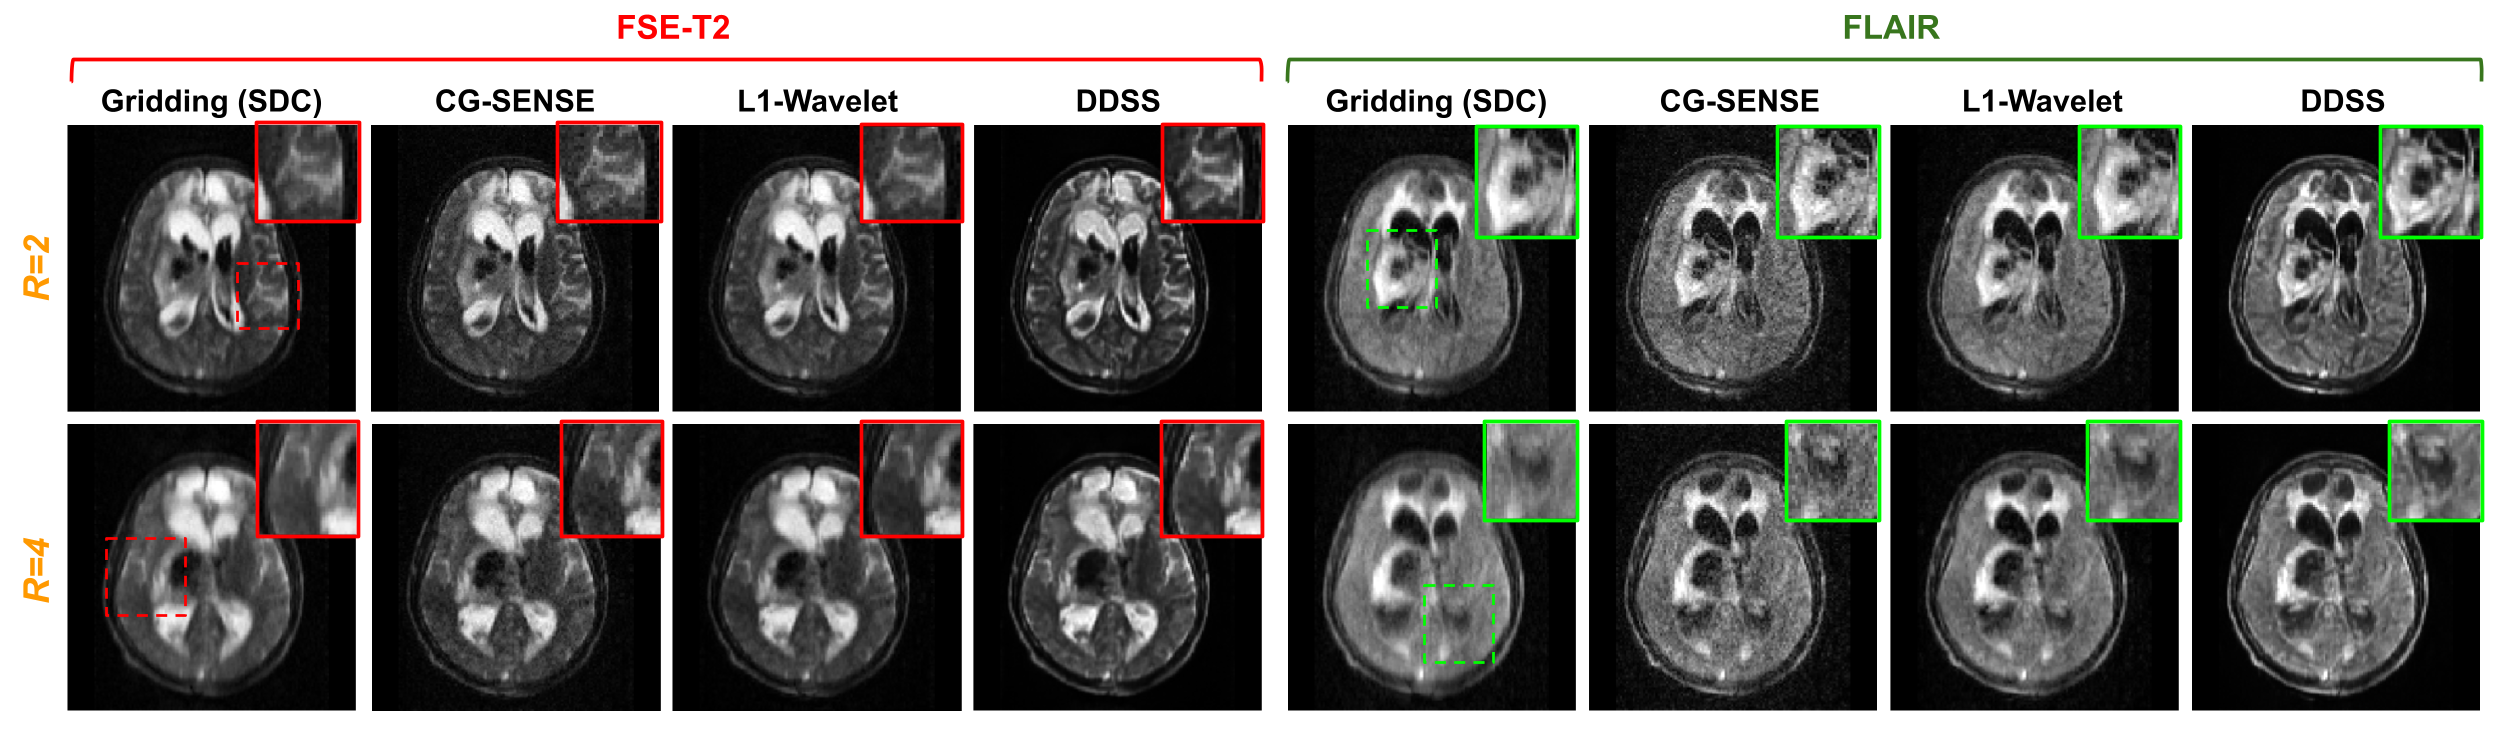

Refer to caption

Fig. 10: Qualitative comparisons of FSE-T2w and FLAIR reconstructions from the real data acquired from a low-field (64mT) MRI system. The subject was diagnosed with a hemorrhagic stroke with associated midline shift. The DDSS reconstruction is compared to Gridding, L1-Wavelet, and CG-SENSE [30] reconstructions of this subject under both R=2 and R=4 acceleration factors.

Qualitative results are presented in Fig. 9 and Fig. 10, where we visualize results from FSE-T2w and FLAIR scans of two subjects presenting with hemorrhagic strokes. In addition to visualizing the CG-SENSE reconstruction, we also visualize the Gridding and L1-Wavelet reconstruction for qualitative comparisons. As we can see from Fig. 9 with R=2, the Gridding reconstructions suffer from blurring due to the accelerated data acquisition protocols. While the L1-Wavelet and CG-SENSE methods can reduce blurring, the proposed self-supervised DDSS reconstructions produce much sharper image quality leading to enhanced visualization of neuroanatomy. Similar observation are made in Fig. 10, where DDSS provides reconstructions with better contrast, sharpness, and lower noise under both R=2 and R=4 acceleration factors.